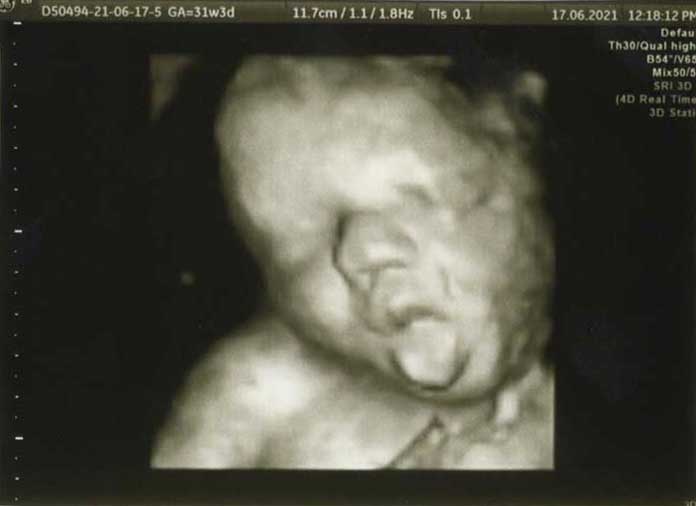

3D/4D HD LIVE

Στο ιατρείο μας προσφέρουμε υψηλής ευκρίνειας 3D και 4D τεχνολογία απεικόνισης του εμβρύου. Η τεχνολογία αυτή αποτελεί ένα ακόμα σημαντικό διαγνωστικό όπλο στη φαρέτρα του προγεννητικού ελέγχου, ενώ ταυτόχρονα ενισχύει την ανάπτυξη του δεσμού ανάμεσα στους μελλοντικούς γονείς και το μωρό τους.